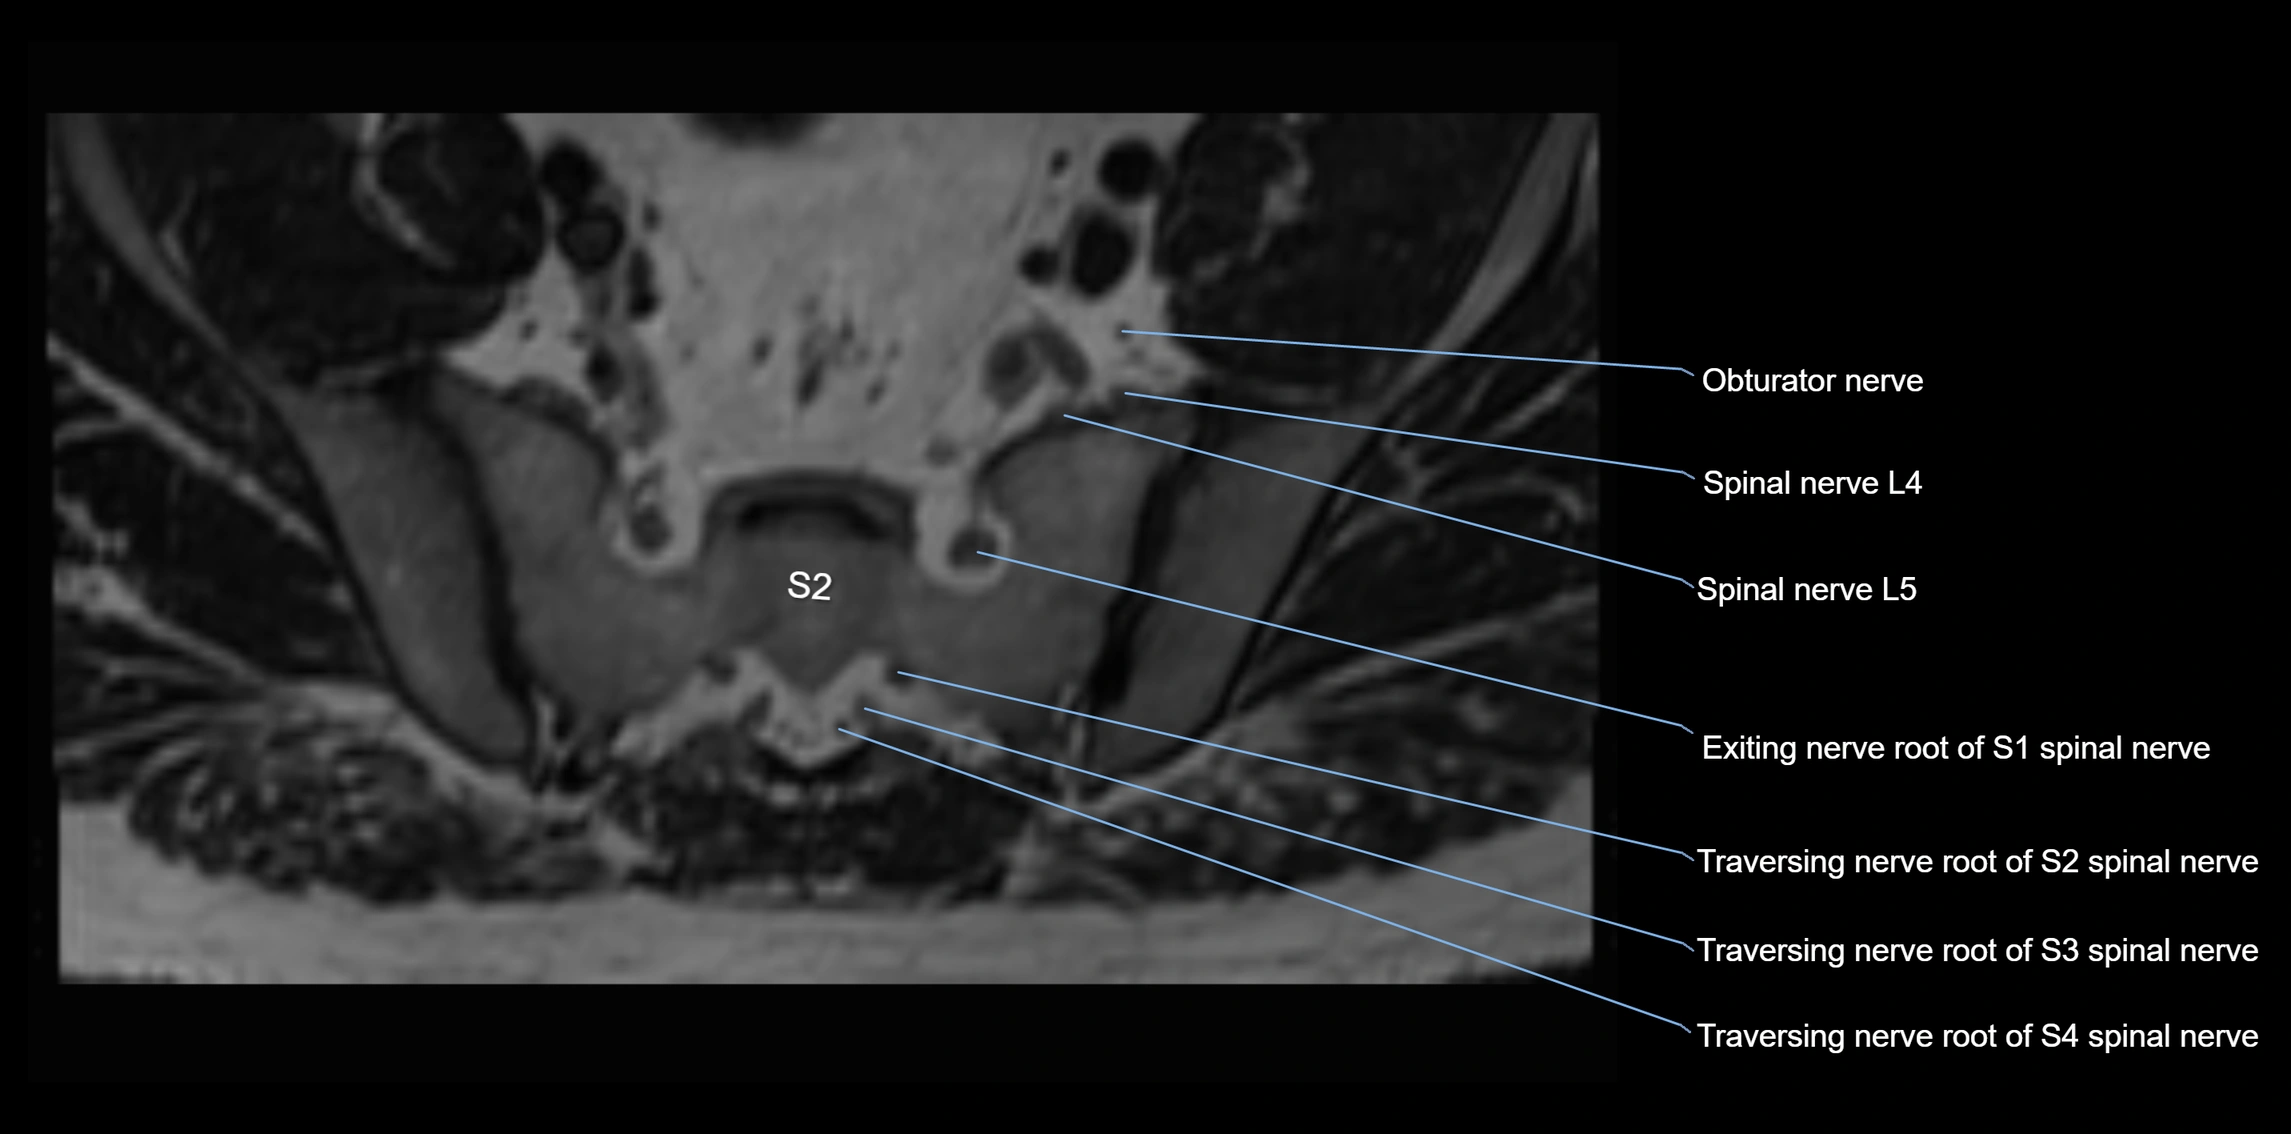

MRI image

image